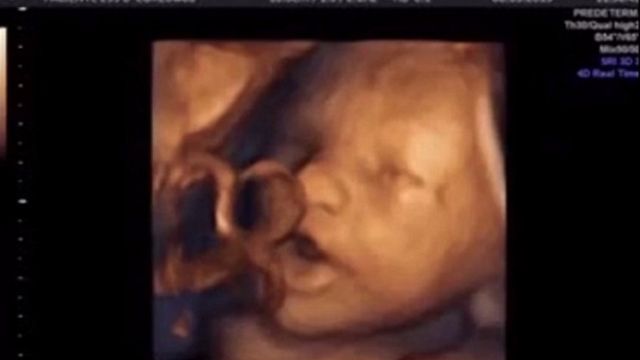

Un bimbo può ascoltare la musica quando è ancora nella pancia della madre. Lo dimostra un video degli scienziati dell'Istituto Marques di Barcellona. La scoperta permette di escludere la sordità del neonato ancora prima che nasca.

Un bimbo di circa quattro mesi reagisce ai suoni e muove la bocca come se volesse cantare.